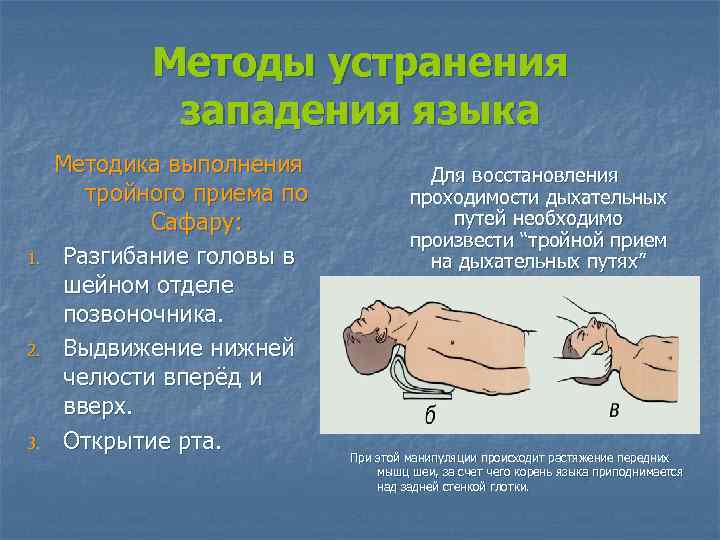

Методы устранения западения языка 1. 2. 3. Методика выполнения тройного приема по Сафару: Разгибание головы в шейном отделе позвоночника. Выдвижение нижней челюсти вперёд и вверх. Открытие рта. Для восстановления проходимости дыхательных путей необходимо произвести “тройной прием на дыхательных путях” При этой манипуляции происходит растяжение передних мышц шеи, за счет чего корень языка приподнимается над задней стенкой глотки.